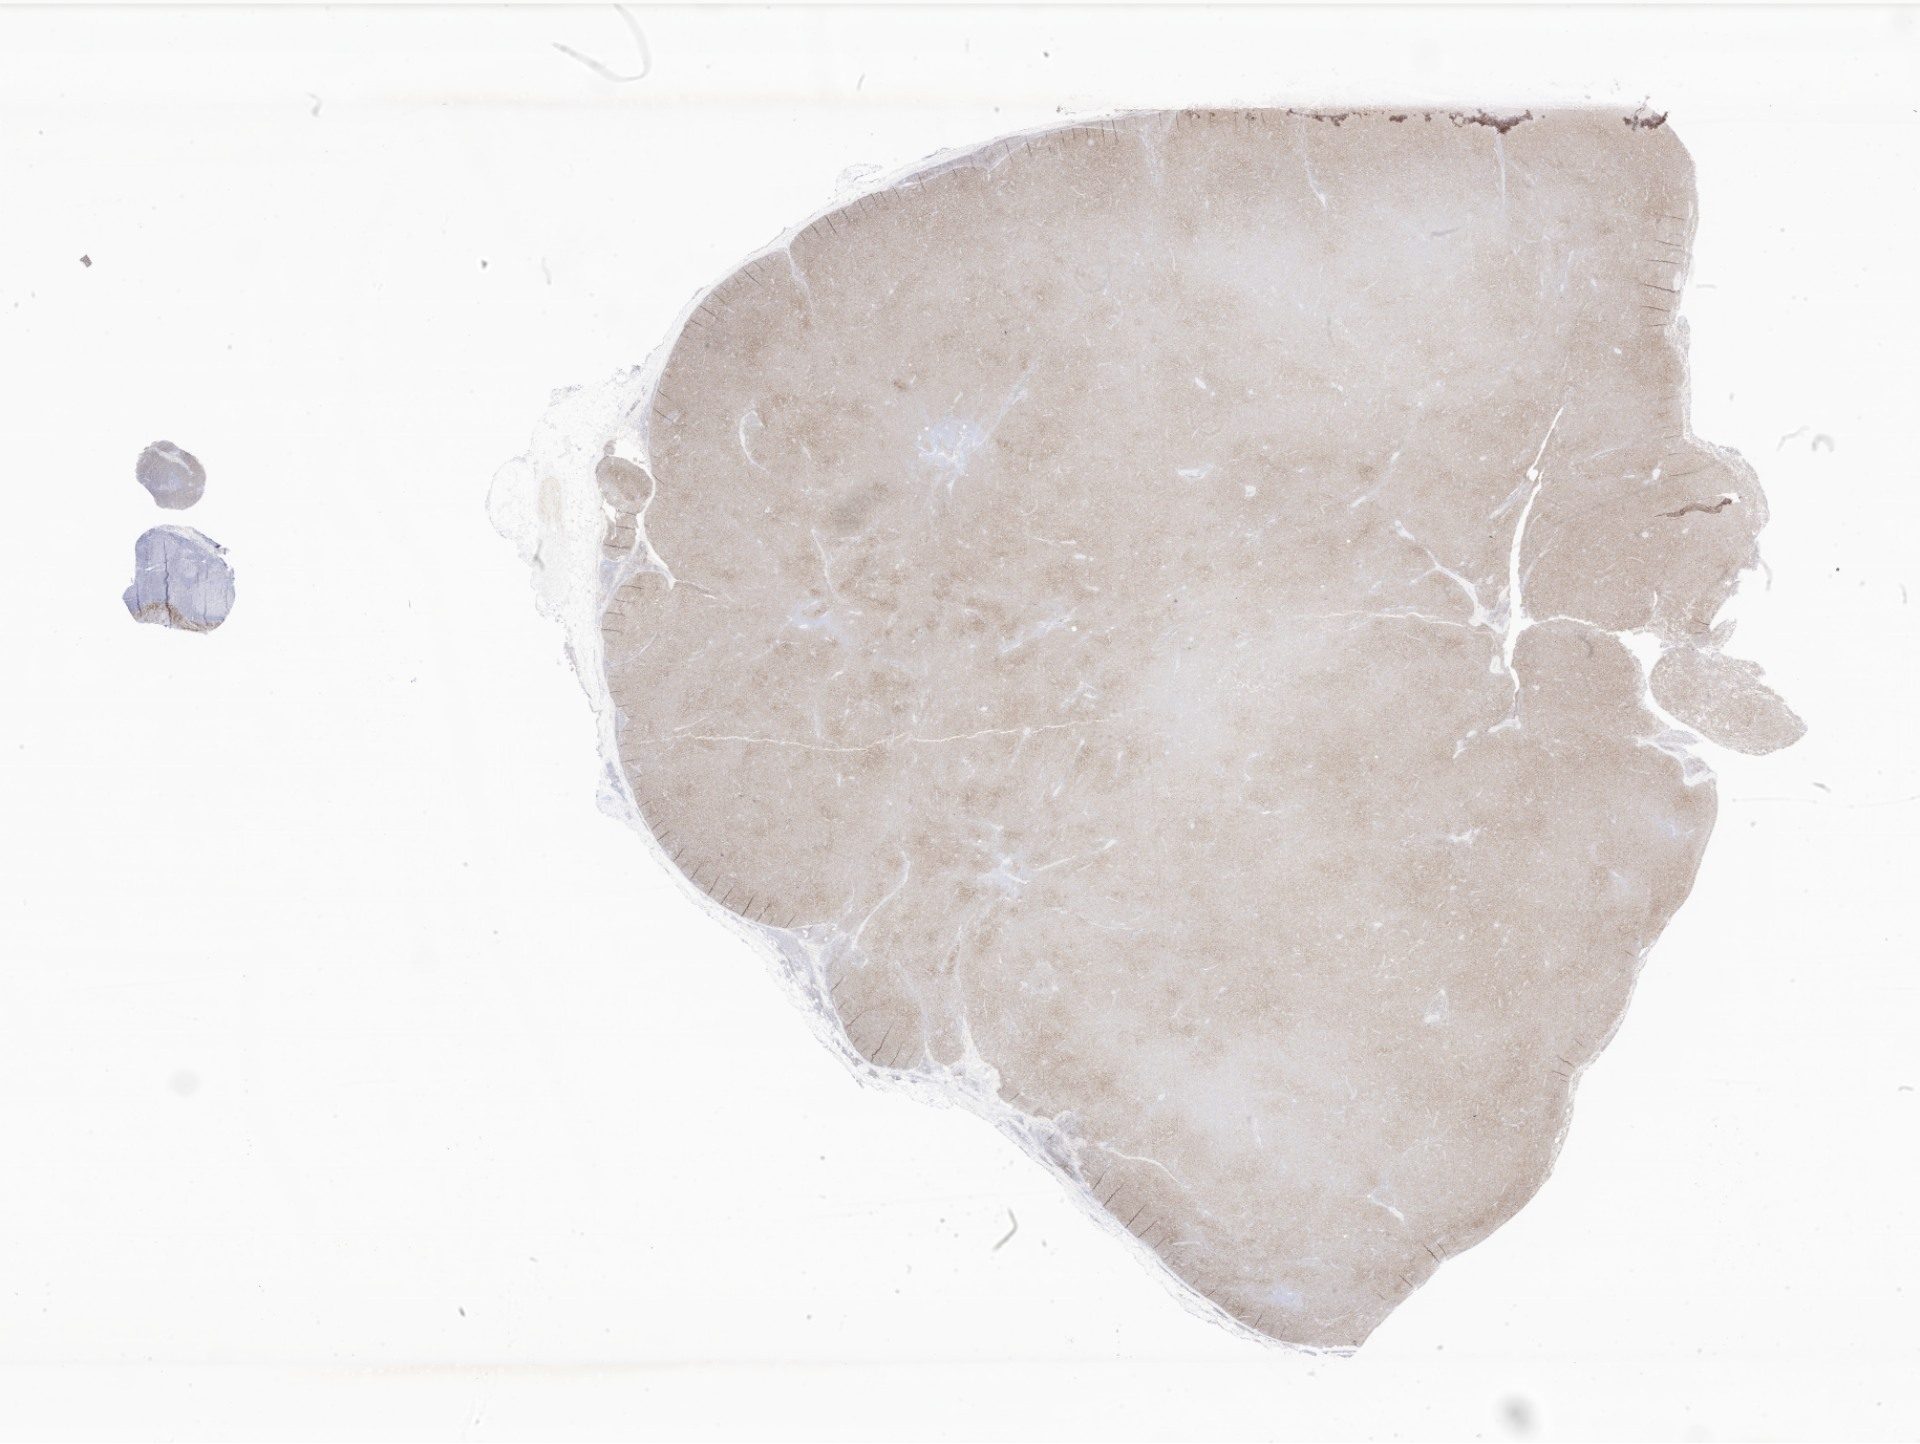

CD5.svs

116783

x

88098

@

40X